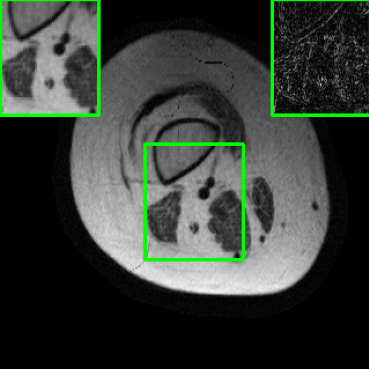

Results for the DIDN-based Reconstructor: To demonstrate adaptability to different network architectures, Table II compares reconstruction performance on the test set with the DIDN denoiser-based MoDL architecture. Average PSNR values with LONDN-MRI are compared to those with networks trained globally at different training set sizes. We ran only iteration of LONDN-MRI, where the reconstruction with a pre-trained (global) network was used to find neighbors. PSNR values for the oracle LONDN-MRI reconstructor are also shown. The overall performances with the DIDN-based architectures are better than with the UNet-based unrolled networks. The PSNRs for LONDN-MRI are consistently and similarly better than for the globally trained network across the different training set sizes considered, indicating potential for LONDN-MRI in improving state-of-the-art models. Fig. 6 visually compares reconstructions and reconstruction errors (in zoomed in region) for different methods. We can see that the LONDN reconstructors capture the original image features more sharply and accurately than the globally learned reconstruction.

| Ground Truth | Global | LONDN-MRI | Oracle |

| (1 iteration) | |||

![]() |

| PSNR = dB | PSNR = 34.15 dB | PSNR = 34.46 dB | PSNR = 34.54 dB |